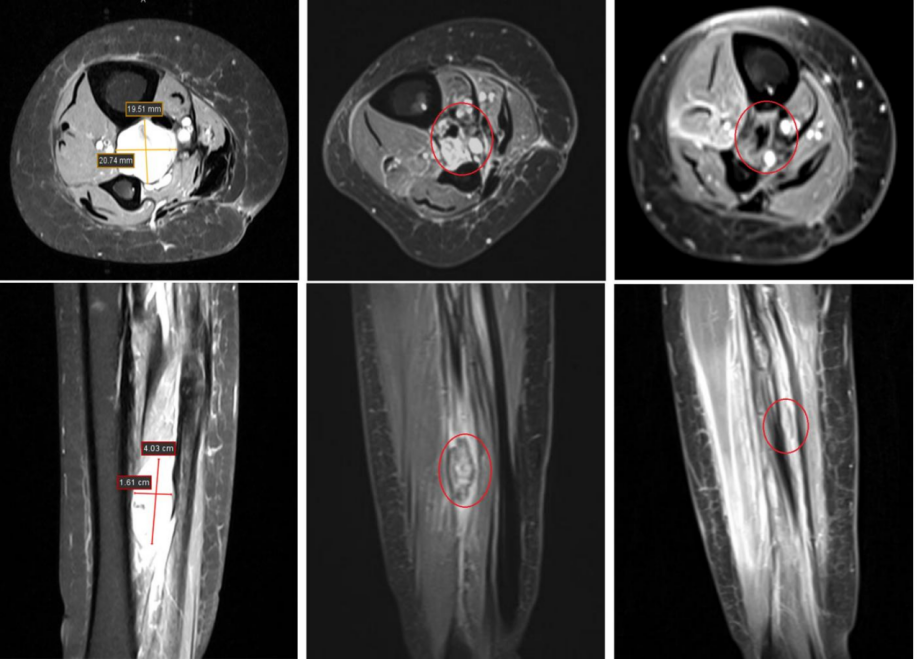

疗效:治疗后肿瘤明显缩小。治疗后60天达到部分缓解(PR),肿瘤直径从42mm缩小至22mm。治疗后120天达到完全缓解(CR),肿瘤完全消失(图4)。治疗后270天的MRI(图5)显示无复发迹象。不良反应:治疗后30天仅出现1级放射性皮炎(轻度红斑和干性脱屑,见图3),未观察到≥2级的急性毒性反应。

图4. 治疗前后影像对比

(对比治疗前、治疗后60天(PR)和120天(CR)的影像学变化。)

图5. 治疗后270天MRI随访

(展示治疗后270天的MRI图像,显示原肿瘤区域无异常信号,证实完全缓解。)